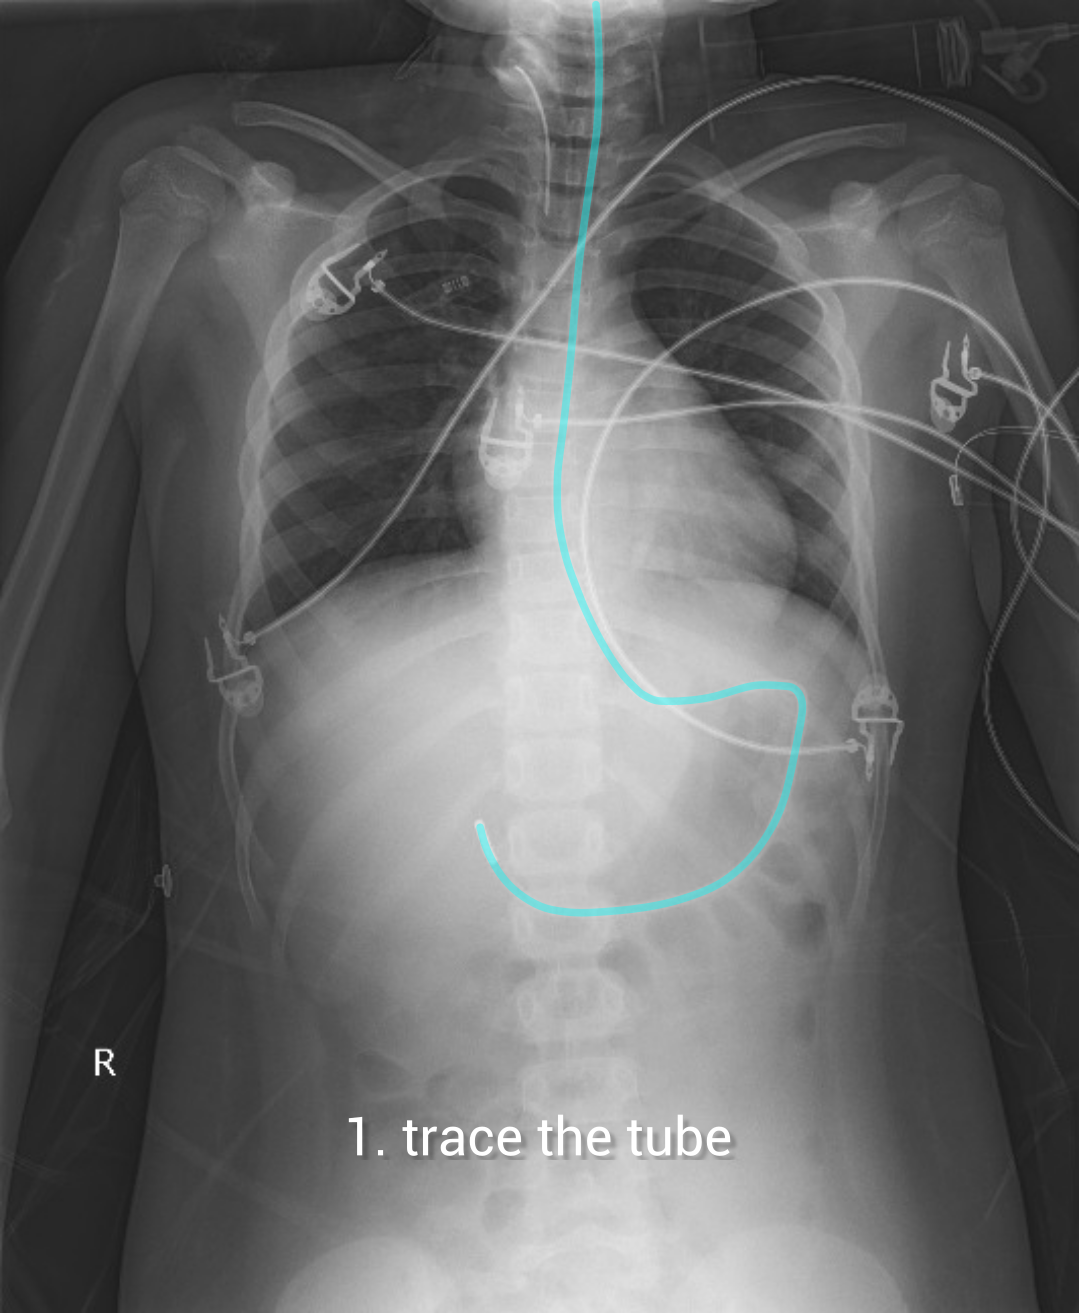

Chest X Ray For Ng Tube Placement . When checking ng tube position, the tube should be seen to pass into the area underneath. In surgical practice, the best and the most accurate method is intraoperative ngt insertion with manual control. To conclude, ngt tube placement can. The tube should pass in the midline below the level of the carina and diaphragm. A correctly placed nasogastric tube should 10: Descend in the midline, following the path of the esophagus and avoiding.

The tube should pass in the midline below the level of the carina and diaphragm. A correctly placed nasogastric tube should 10: Descend in the midline, following the path of the esophagus and avoiding. To conclude, ngt tube placement can. In surgical practice, the best and the most accurate method is intraoperative ngt insertion with manual control. When checking ng tube position, the tube should be seen to pass into the area underneath.